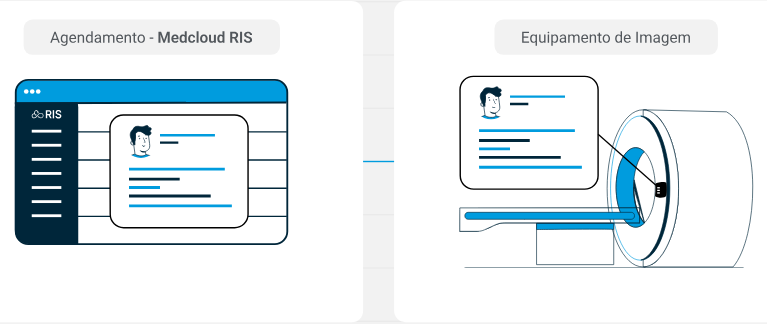

Visualiza la lista de trabajo en tiempo real, puedes consultar tu turno desde una pantalla de información.

Usando Medcloud Connect envías imágenes y estudios a la nube usando una página web. Seleccionar y arrastrar. Así de simple.